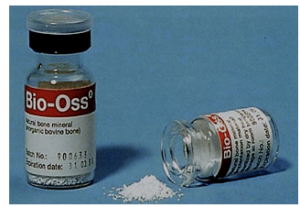

②骨充填剤です。

③抜歯窩に(根のあった穴に) ②の骨粉を入れます。